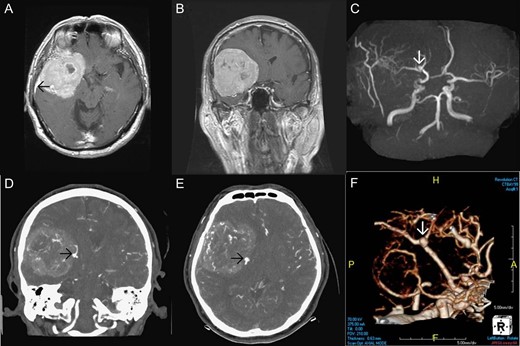

Brain magnetic resonance imaging (MRI) and MR angiography (MRA) revealed a large extraaxial well-circumscribed mass lesion with some calcification/hemorrhage in the right frontal–temporal convexity, abutting the skull bone, measured ~7.7 cm in maximal diameter. Post-contrast study showed good and somewhat heterogeneous enhancement with dural tail sign. Incidentally, a suspicious small aneurysm in bifurcation of the right MCA was found (Fig. 1). CT angiography (CTA) of brain was further arranged which demonstrated a wide-based saccular aneurysm in bifurcation of the right MCA, ~4.7 mm in size, abutting the tumor with dome tilting laterally, anteriorly and inferiorly (Fig. 1). Due to the significant mass effect of the brain tumor and the progressive neurological decline of the patient, surgical resection of the tumor and clipping of the aneurysm in one operation was planned.

Pre-operative imaging. Axial T1 weighted image post gadolinium enhancement (A), coronal T1 weighted image post gadolinium enhancement (B) showing a large extraaxial well-circumscribed mass lesion in the right frontal–temporal convexity, abutting the skull bone with good enhancement and dural tail sign (black arrow in Fig. 1A). MRA (C) showing a suspicious small aneurysm in bifurcation of the right middle cerebral artery (white arrow). CTA of brain coronal view (D), axial view (E), 3D reconstruction (F) showing a wide-based saccular aneurysm in bifurcation of the right middle cerebral artery abutting the tumor with dome tilting laterally, anteriorly and inferiorly.